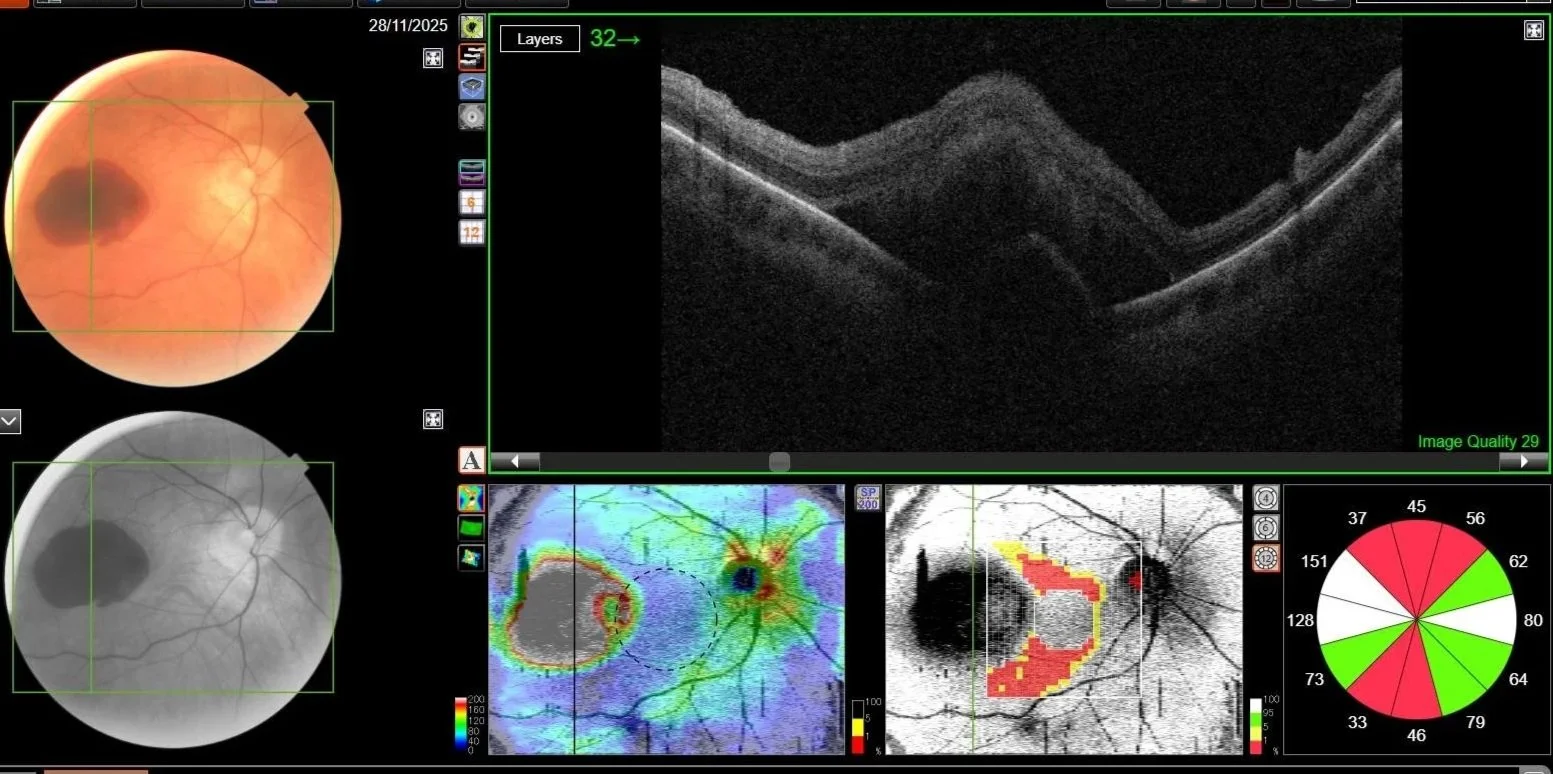

Enhanced OCT Scans

Also known as Ocular Coherence Tomography (OCT), this is an advanced eye scan for people of all ages. In a similar way to ultrasound, OCT uses light rather than sound waves to illustrate the different layers that make up the back of the eye.

The OCT machine captures both a retinal photograph and a retinal scan of the back of the eye, allowing us to rapidly diagnose a number of common eye conditions (i.e. macular degeneration, glaucoma and diabetes).

The scan is non-invasive, painless, simple and quick. With every scan the software can automatically detect even the subtlest changes to the retina, giving you an invaluable record of the health of your eyes.